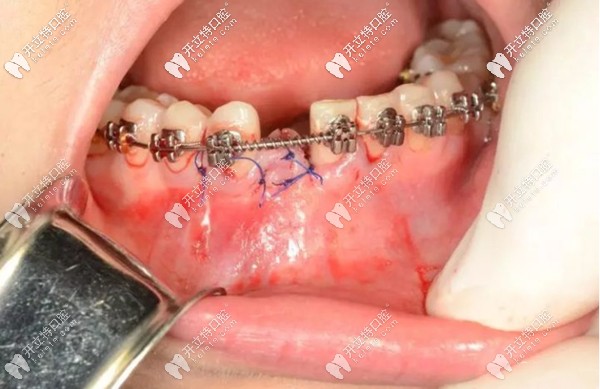

就例如,像我這種情況,下門牙先天缺失一顆,牙槽骨骨量充沛,在正畸進行到一半,也就是可以容納一顆種植體的時候,由種植醫(yī)生為我做了微創(chuàng)種植手術(shù)。

然后,將種植手術(shù)部位進行縫合,靜待植體和牙槽骨的結(jié)合,預(yù)計3個月左右的時間。之后安裝基臺、牙冠,這顆種植牙大概需要半年左右的時間才能“大功告成”。

而做種植牙這段時間,對我的牙齒正畸治療也不會有太大影響。